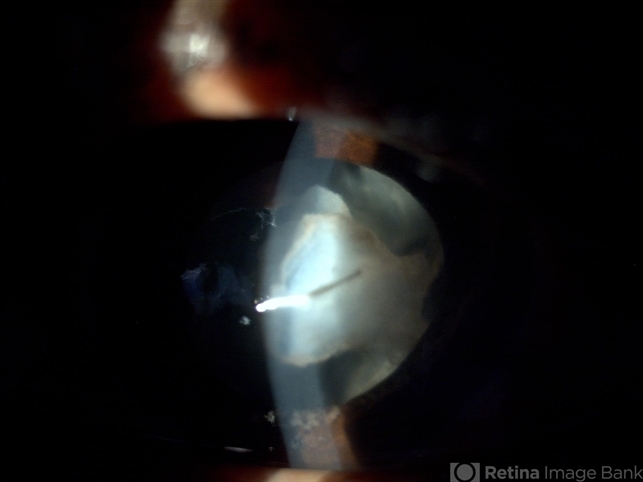

- intraocular foreign body

- A 28-year-old male presented loss of vision following injury during work.